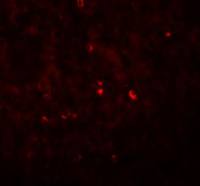

Immunohistochemical analysis of paraffin-embedded human hepatoma, using ACOT12(GTX123722) antibody at 1:500 dilution.

Antigen Retrieval: Trilogy™ (EDTA based, pH 8.0) buffer, 15min